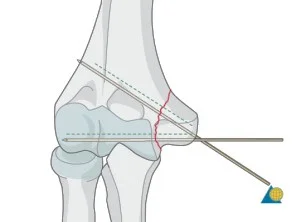

Closed reduction 1. Traction in the line of the bone

-

Pressing fragment into reduced position

Disimpaction